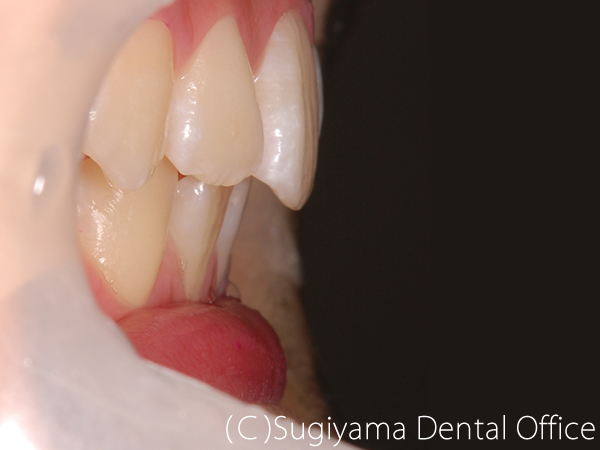

術前症例写真

術後症例写真

上の歯は1本後ろに生えていたうえに、下あごが出ていた男性の患者さんです。

顎の手術や抜歯をせずに矯正治療を終えることができました。